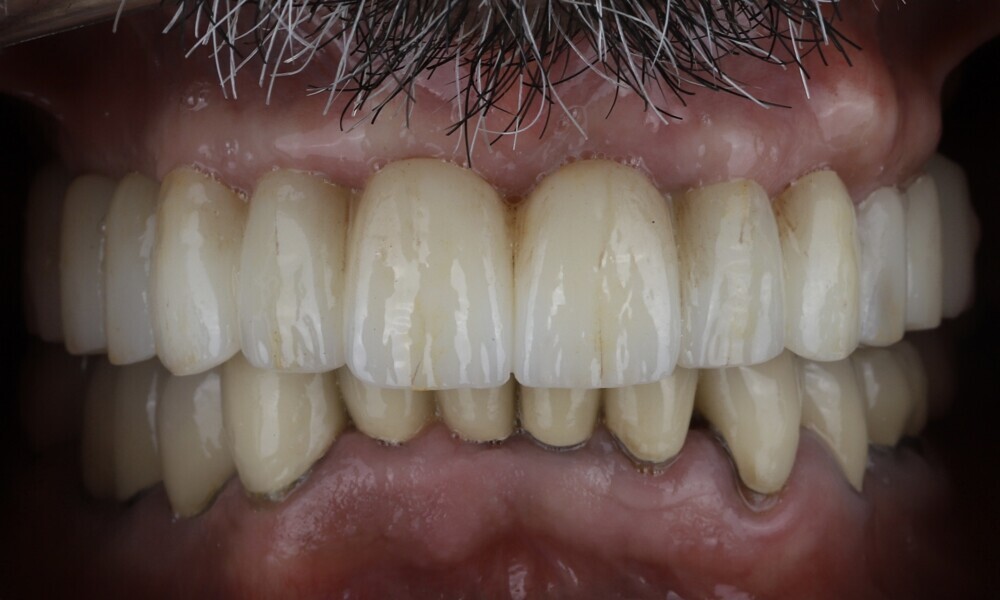

The delivery of the final prosthesis was then performed, and the aesthetics, occlusion and function were verified (Figs. 51–55). The panoramic control radiograph showed that all measurements were within expected ranges (Fig. 56).

At the 18-month follow-up after completing the treatment, an intra-oral, extra-oral and radiographic evaluation were performed. No pathologies were observed, and the results remained stable over time (Figs. 57–62). The patient expressed his satisfaction with the treatment outcomes, stating, “Seeing my new smile before starting the procedure was a game-changer. I was confident from the beginning that my final result would be as I had imagined.”

The combination of Straumann BLX implants with the Straumann RevEX scan bodies for a full monolithic design and integrated into a comprehensive Smilecloud digital workflow yielded favourable treatment outcomes for full-arch rehabilitation in this case. The seamless coordination between the surgical and prosthetic phases, facilitated by state-of-the-art digital technologies, enhanced precision, efficiency, and patient comfort and satisfaction. This case underscores the important role of digital dentistry in ensuring reliable and aesthetically satisfying results in implant therapy.